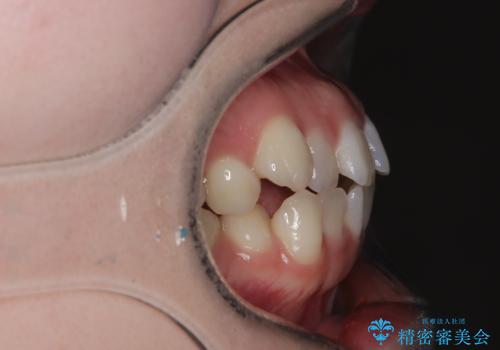

- 右上の八重歯と歯並びのデコボコを気にされて来院されました。精密な検査の結果、歯列のスペースがわずかに不足していることが判明。患者様の「抜歯を避けたい」というご希望を最大限に尊重し、アンカースクリュー(TAD)を用いて奥歯(臼歯部)全体を後方へ移動させることで、八重歯が並ぶスペースを確保する治療計画を立案しました。装置にはワイヤー矯正を使用し、確実で効率的な歯の移動を目指します。

今回のワイヤー矯正治療では、抜歯せずに歯を並べるスペースを作るため、特殊な小さなインプラントであるアンカースクリュー(TAD)を一時的に使用しました。このアンカースクリューを固定源として、奥歯(臼歯部)全体を後方へ遠心移動させました。従来の矯正では難しかったこの奥歯の移動を確実に行うことで、前歯の八重歯を適切な位置に並べるスペースを確保。治療の結果、抜歯することなく右上の八重歯と叢生が解消され、機能的にも審美的にも整った美しい歯並びを獲得していただけました。